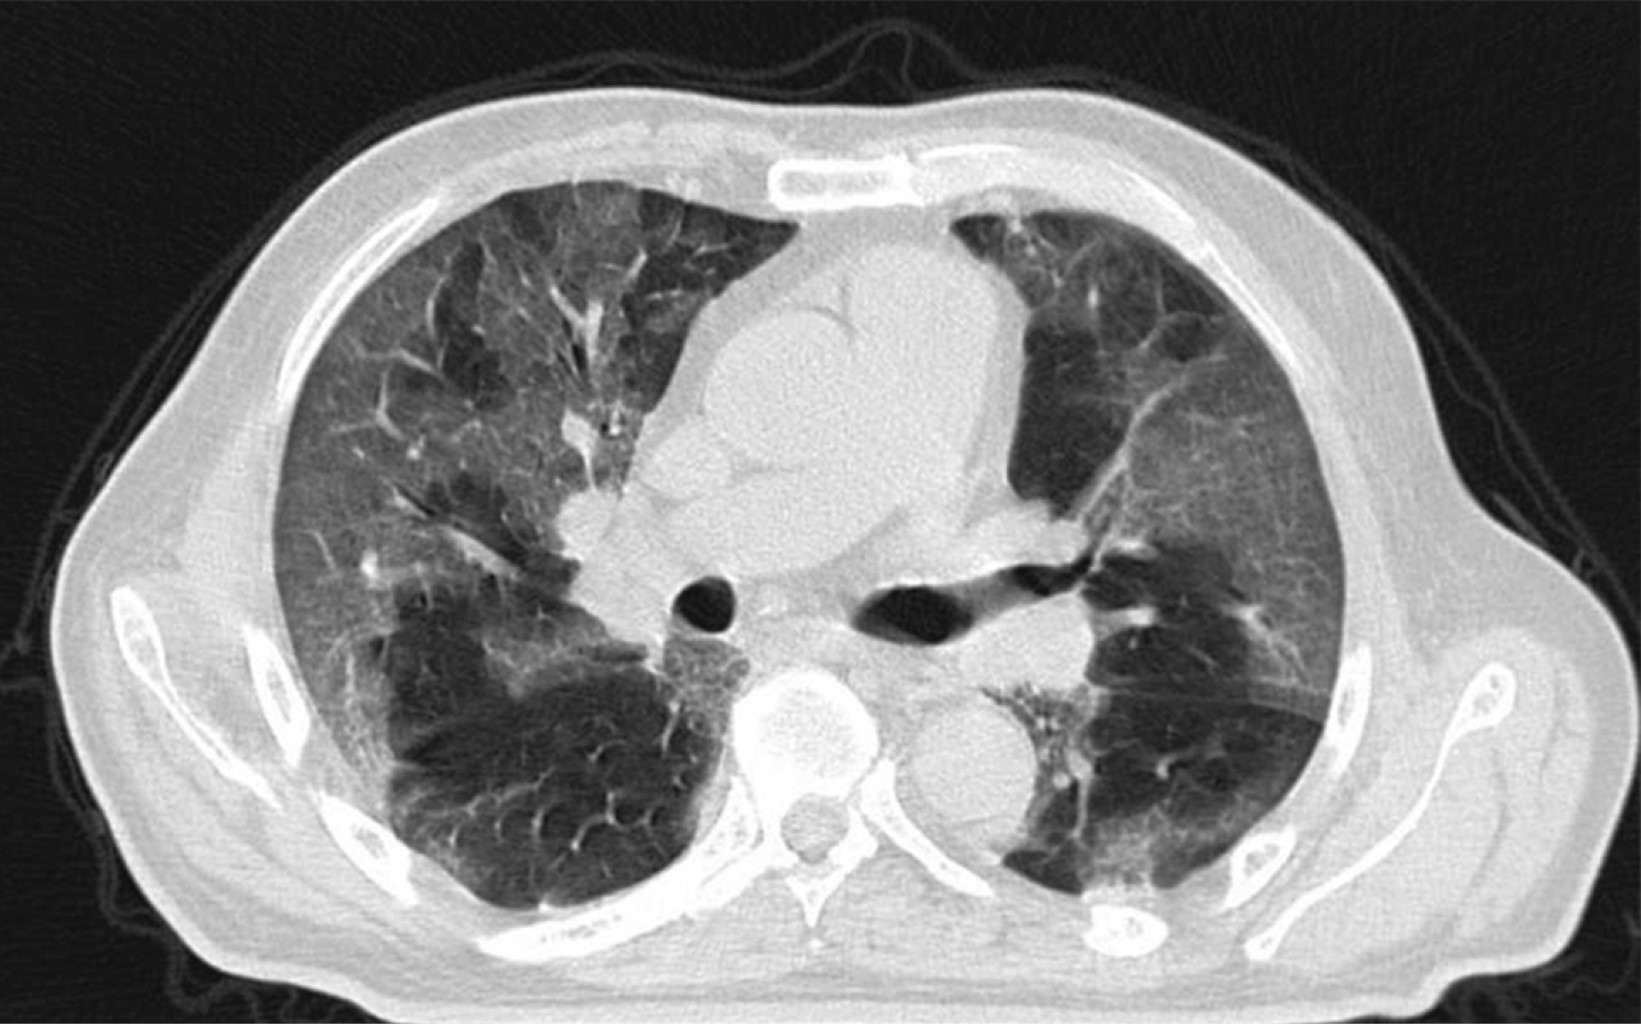

A 69-year-old male patient with a history of type 2 diabetes mellitus was treated with metformin and chlorpropamide. He also had hypertension treated with losartan and amlodipine. He presented to the emergency department with headache, chest pain, cough, myalgias, arthralgias, and dyspnea of one-week evolution. On admission, his heart rate was 114 bpm, respiratory rate 24 rpm, oxygen saturation 80% without supplemental oxygen support; his glucose was 587 mg/dl, white blood cells 25,690 cells/mm3, neutrophils 85%, lymphocytes 1.2%, hemoglobin 16.3 g/dl, procalcitonin 3.78 ng/dl, arterial blood gas with a pH of 7.41, pCO2 21 mmHg, PO2 35 mmHg, HCO3 13 mmol/l, oxygen saturation 62%. A rapid antigen test for SARS-CoV-2 was performed, and the result was positive; a CT scan of the chest showed radiological data suggestive of SARS-CoV-2 infection (Figure 1), and management with supplemental oxygen, insulin infusion pump, carbapenem antibiotics, antihypertensives, dexamethasone, and antithrombotic prophylaxis with enoxaparin was started. 48 hours after admission, the patient continued with septic shock, so vasopressor amines were started; an orotracheal intubation was performed and support with invasive mechanical ventilation was initiated. A nasogastric tube (NGT) was placed. After 24 hours of its placement, he presented hematemesis accompanied by abdominal distension, leukocytosis of 40,000 cells/mm3. A simple abdominopelvic CAT scan was performed, which revealed gastric pneumatosis and pneumoperitoneum (Figure 2). An urgent exploratory laparotomy was performed finding necrosis of the greater curvature of the stomach. A vertical gastrectomy was performed with GIA stapler with purple cartridges of 45 and 60 mm (Figure 3); the stapling line was reinforced with continuous a Prolene suture 00; a feeding jejunostomy tube was placed at 60 cm from the Treitz angle and Saratoga drains were left in place. Twenty-four hours later, the patient had hemodynamic stability, vasopressor amines were suspended, and enteral nutrition with an elemental diet was started. On the fifth postoperative day, the patient showed adequate tolerance to the enteral diet through jejunostomy. The methylene blue test was performed through the nasogastric tube showing no evidence of leaks; the white blood cell count decreased to 24,000 cells/mm3. Histopathology results were obtained revealing pan mural necrosis associated with arterial thrombosis secondary to microorganisms compatible with Mucor sp.; therefore, management with amphotericin B was initiated (Figures 4 and 5). During follow-up he showed good evolution; an abdominopelvic CT scan with contrast by the nasogastric tube was performed, which ruled out leaks and intra-abdominal collections and corroborated the integrity of the gastric wall; drains were removed, and the patient was discharged from general surgery on day 9 post-surgery, continuing to be managed by the internal medicine service. During the following days of hospitalization, the patient presented cardiovascular and pulmonary deterioration; a urine culture was taken, which showed growing of Candida tropicalis, and a CAT scan of the skull, thorax, and abdominopelvic with oral contrast was performed (Figures 6 and 7), The patient continued without evidence of abdominal leaks, rhino-cerebral and pulmonary mucormycosis were ruled out. A probable superimposed bacterial pneumonia and interstitial pneumopathy secondary to COVID-19 were reported. He showed persistent clinical deterioration and refractory shock and 29 days after admission.

On admission, the patient did not report any abdominal symptoms, so gastrointestinal involvement was not suspected. Subsequently, intravenous sedation and orotracheal intubation were performed, making it impossible for the patient to manifest gastric involvement. The only sign the patient presented was hematemesis 24 hours after the nasogastric tube placement, which ruled out the possibility of healthcare-associated mucormycosis since 24 hours are not enough to achieve the introduction, inoculation, and growing of the fungus. This led to the hypothesis that the patient acquired the fungal infection in his community. The diagnosis may be suspected by endoscopic findings, such as a fungal mass or necrotic lesions covering ulcerated areas that may perforate tissues and cause peritonitis.2 Often, the study protocol is initiated in the presence of an intra-abdominal abscess; the diagnosis can be made by biopsy of the suspicious area during surgery or endoscopy.7 Few samples are usually sent for culture,2 and those sent are positive in only 30%, in addition, specialized culture media such as potato dextrose agar are required for fungal growing.12 Confirmatory molecular tests that may detect surface antigens are also required, but they are not yet available.2 CT findings may include focal or diffuse thickening of the gastric wall, pneumatosis with decreased wall enhancement on contrast administration (emphysematous gastritis) secondary to ischemia and necrosis, adjacent collections, wall necrosis with focal disruption or perforation, and rarely, pneumoperitoneum.13 When hematemesis occurs, the next diagnostic step should be an upper endoscopy. However, the abdominal distention presented by the patient suggested a high probability of perforation of the hollow viscera, so initially, a CT scan of the abdomen was performed. A surgical emergency was considered when reporting gastric pneumatosis and pneumoperitoneum, ruling out an endoscopy. Exploratory laparotomy allows direct exploration of the stomach and partial resection of the stomach as a diagnostic and therapeutic measure. Treatment consists of antifungal and urgent surgical debridement since necrotic tissue's presence will affect the antifungal's penetration to the tissues; additionally, aggressive medical support for comorbidities should be provided.14 Intravenous liposomal amphotericin B is the treatment of choice. It is more effective than conventional amphotericin B.15 Delaying the initiation of amphotericin for more than six days, doubles mortality.4 Although most of literature favors aggressive surgical treatment, we opted for a more conservative treatment by preserving a portion of the stomach and performing only a vertical gastrectomy since macroscopic inspection showed a clear demarcation between necrotic and viable tissues. We consider that the surgical treatment we performed was correct since, in the post-surgical follow-up, the patient had a good evolution; the methylene-blue test and the two abdominal CT scans with contrast in the stomach through the nasogastric tube allowed us to verify the integrity of the suture line from the first post-surgical day until the day of his death. The sample sent to pathology allowed to make the diagnosis and thus initiate targeted therapy with amphotericin B, and since no fungal infection by Mucor sp. at any other organic level was found, the cause of death was attributed to nosocomial infectious complications at the pulmonary and urinary level.

Figure 2